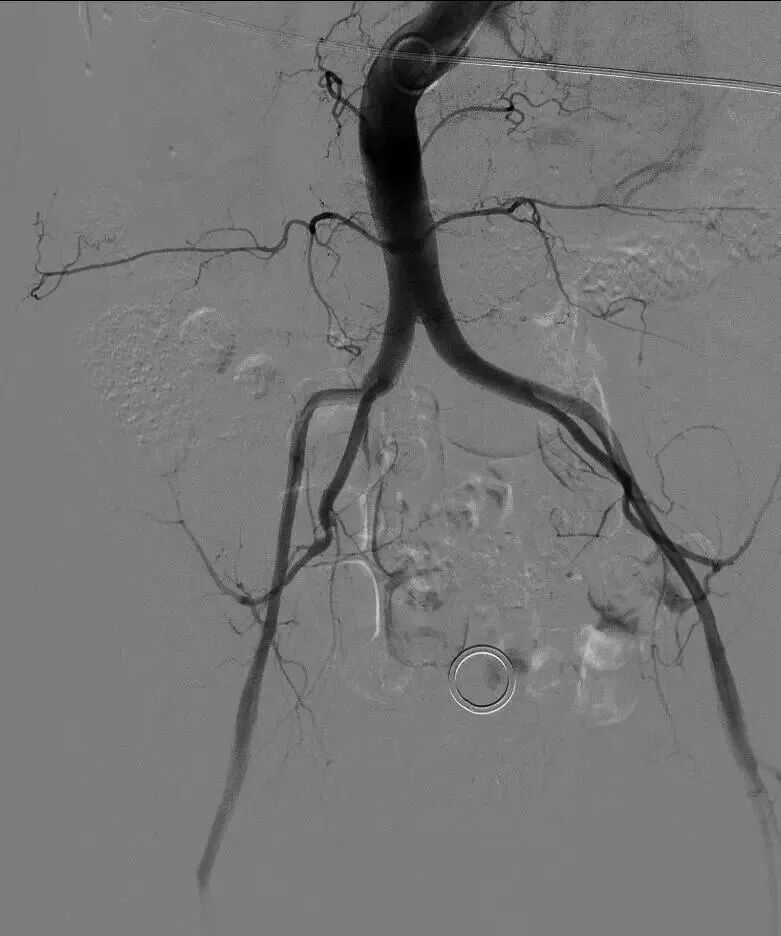

73岁的患者于婆婆(化名)因重度主动脉瓣狭窄入院,突发急性失代偿性心衰合并心源性休克,血压持续走低,多器官功能急剧恶化,此类患者24小时内死亡率超50%,急诊TAVR是唯一的生存希望。术中造影发现,患者双侧股动脉最细处直径不足3毫米,远达不到手术输送鞘管的最低要求,常规入路完全阻断;开胸心尖入路创伤过大,休克状态下的患者根本无法耐受,所有常规方案均不可行。更棘手的是,患者病情危重无法完成术前主动脉CTA检查,手术团队只能在“半盲”状态下,仅凭有限影像和临床经验,完成毫米级的精准操作。

生死关头,在与患者家属充分沟通后,心血管诊疗中心一病区主任敖钦主任医师、主诊组长曹俊达副主任医师迅速集结心内、胸外、超声、麻醉、介入护理等多学科团队,并调动重症ECMO团队全程为手术保驾护航。团队选择经左侧颈总动脉入路,而这一术式,在急诊抢救、无术前CTA精准导航的双重极限条件下,无疑是一场超高难度的生死挑战。颈动脉是大脑供血命脉,操作稍有闪失即可引发灾难性卒中;无CTA就无法评估血管内斑块、走行异常、主动脉弓部情况,每一步都是“雷区”。心胸外科诊疗中心陈世雄副主任医师团队精准暴露左侧颈总动脉,穿刺、置管一气呵成。术中仅凭食道超声即时评估选择瓣膜型号,导丝“盲穿”穿过主动脉弓进入左心室。从穿刺到瓣膜释放,全程仅用时13分钟。造影显示瓣膜位置完美,无瓣周漏,冠脉通畅。术后患者血压即刻改善,次日心功能明显恢复,第五天转回普通病房,康复顺利。